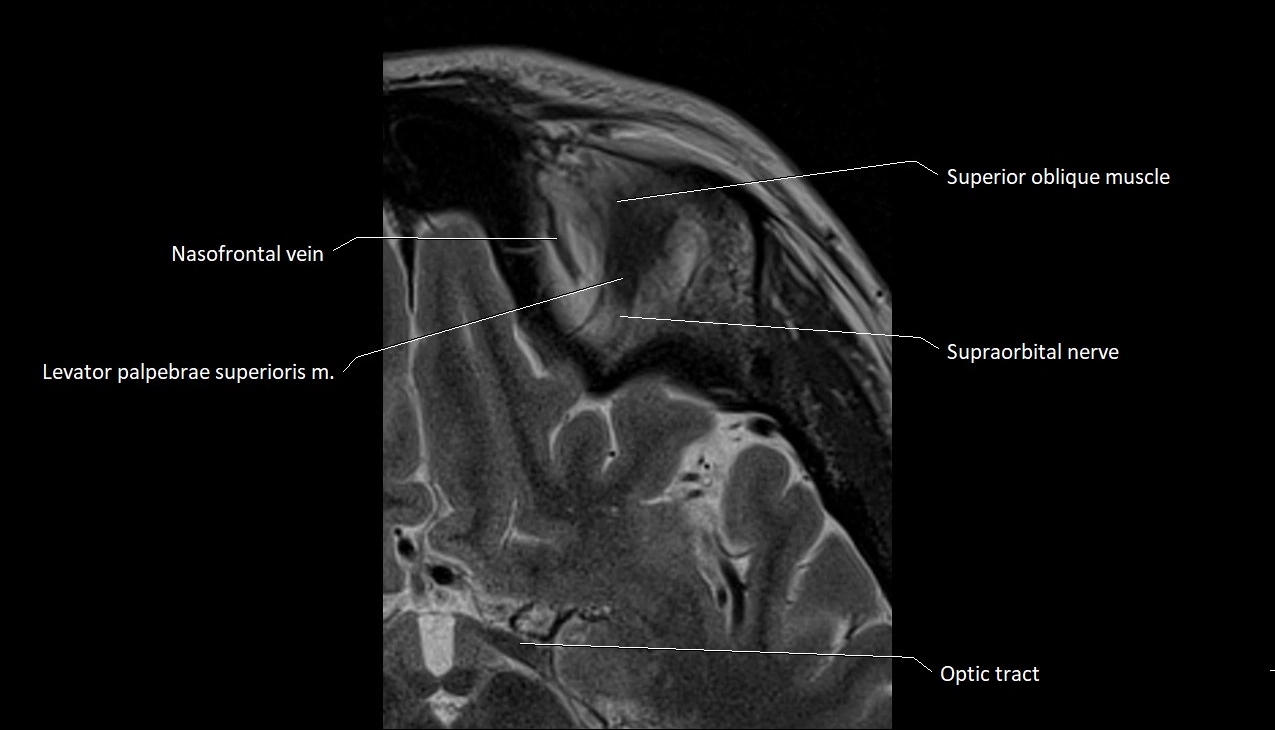

- Superior oblique muscle

- Nasofrontal vein

- Levator palpebrae superioris muscle

- Supraorbital nerve

- Orbital part of optic nerve